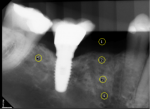

At 1-, 4-, and 12-week postoperative visits, photographs of the surgical sites were taken and wound healing was evaluated. The 6-month postoperative visit included reviews of medical history, oral examination, and digital periapical radiography. After local anesthesia, a full-thickness flap was reflected. The buccolingual bony dimensions of the ridge were measured again using a periodontal probe by the same examiner (Figure 1). Later, a dental implant would be placed.

Regarding image acquisition and analysis, a reference aluminum step wedge (Margraf Dental Mfg. Inc., margrafdental.com) was fixed on the digital sensor (RVG 6100, Carestream Dental, carestreamdental.com), avoiding the superimposition over the region of interest. A handheld x-ray unit (NOMAD Pro™, Aribex Inc., aribex.com) was used for exposures. Density variations produced by the exposures were addressed and digitally similar step-wedge densities on radiographic images were provided.8 Images were exported in TIFF format and saved in a desktop folder, and were later imported into ImageJ software (National Institutes of Health) to study the mean grey values. On the images, three small circles similar in size were created in the center of the previous extraction socket at the crest, midroot, and apex (Figure 2 [circles 2 through 4]). Two independent calibrated examiners recorded the grey-value measurements at these sites.